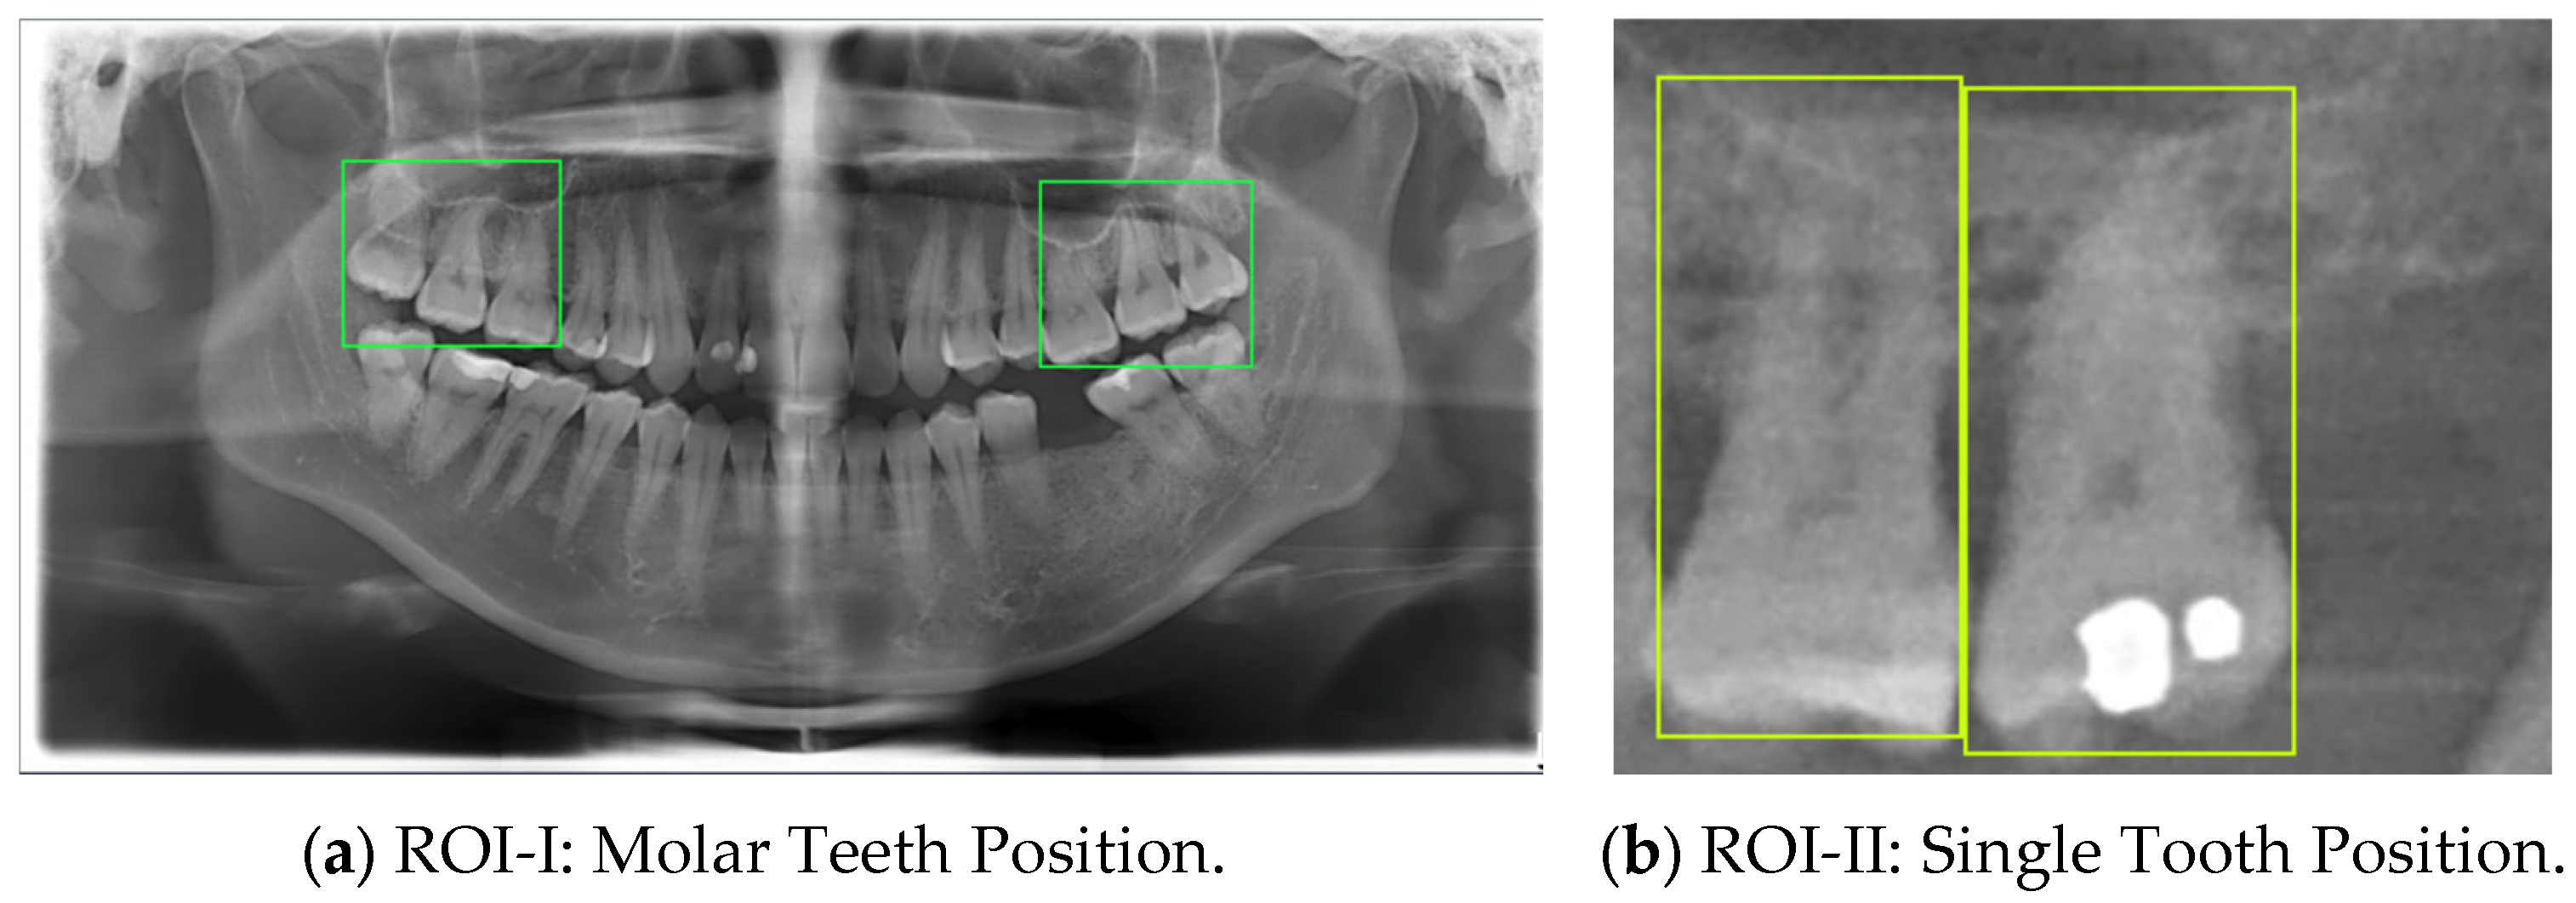

In this study, the maxillary region of each DPR image was annotated at the far-left and far-right sides, with the marked positions defined as the Region of Interest (ROI) for sinus invasion lesions, referred to as ROI-I. This region includes teeth #16, #17, #18, #26, #27, and #28, based on the Fédération Dentaire Internationale (FDI) numbering system [23], as shown in Figure 2. Single-tooth regions were further segmented from ROI-I to train the final classification model, defining them as ROI-II. This step aims to generate the dataset required for model training, enabling the model to be trained in more refined regions to enhance classification performance and accuracy.

2.1.1. ROI-I and ROI-II Annotation

Since the lesion areas near the sinus floor are located at the posterior left and right maxillary regions, it is essential to segment the Region of Interest (ROI) from DPR images before conducting lesion analysis. First, ROI-I includes teeth #16, #17, #18, #26, #27, and #28 based on the Fédération Dentaire Internationale (FDI) numbering system. This region is selected using quadrilateral bounding boxes, as illustrated in Figure 3a. This process ensures that ROI-I effectively encompasses potential sinus invasion lesion sites while excluding irrelevant areas, thereby improving the accuracy of subsequent model segmentation. After obtaining ROI-I, individual tooth regions (ROI-II) are further segmented. The precise quadrilateral tool is used for marking, ensuring the inclusion of the sinus line and the single tooth, as shown in Figure 3b. This method accurately captures the alignment and position of lesions, providing high-quality input data for CNN model segmentation and analysis. This two-stage segmentation approach significantly improves the accuracy of detecting whether tooth roots are close to the sinus floor in cases of odontogenic sinusitis, offering more reliable technical support for lesion analysis and assisted diagnosis.

Table 8 demonstrates a comparison of different YOLO model performances. First, YOLO11n has outstanding performance across all metrics in the ROI-I phase, achieving an accuracy of 90.0%. This represents a significant improvement compared to YOLOv8n (70.6%) and YOLOv10n (80.0%) while being slightly higher than YOLOv9n (89.5%). Its precision reached 94.4%, the highest among all models, indicating that YOLO11n effectively minimizes false positive results. The recall was also 94.4%, matching YOLOv9n’s performance. In molar teeth position detection, the image shows two highlighted regions with prediction accuracies of 92% and 91%, indicating consistent performance in molar teeth detection. In the ROI-II phase, YOLO11n achieved the best performance, with an accuracy of 93.2%, precision of 94.8%, and a remarkably high recall of 98.2%. For the single tooth position detection, the highlighted regions show prediction accuracies of 89% and 99%, demonstrating the model’s capability to precisely identify individual teeth. These metrics indicate that YOLO11n excels in classifying target regions and detecting all target instances. Additionally, its F1 score reached 98.2%, demonstrating exceptional capability in balancing precision and recall, further solidifying its advantage in detection and classification tasks.

Figure 3. DPR image annotation.

Bioengineering 12 00134 g003